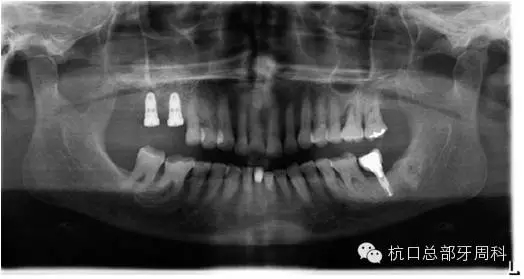

初診時(shí)全景片2011.7

112.webp.jpg

全景片:大范圍火山口樣/彈坑樣骨缺損

CT:左下缺牙區(qū)及部分升支存在骨破壞